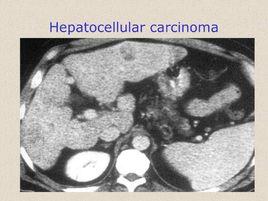

肝細胞性黃疸鑑別診斷需注意臨床症狀和體徵,詢問是否存在伴隨症狀,如發熱、皮疹、皮膚瘙癢、乏力、食慾及尿糞異常、出血傾向以及各器官系統相應症狀。查體應全面細緻,不要有遺漏。特別注意皮膚黏膜黃染的顏色(溶血性黃疸常呈檸檬色,肝細胞性黃疽多為金黃色或淺黃色,阻塞性黃疸多為暗黃色或黃綠色)、淋巴結、肝膽脾有無腫大等。不同原發病體徵不同,肝腫大並有門脈高壓者多為肝硬化失代償,肝癌並發黃疸患者體檢可察肝腫大並伴有結節感,蜘蛛痣則見於慢性肝炎和肝硬化。肝細胞性黃疸的病程也可作為診斷的參考,如甲型、戊型病毒性肝炎的黃疸一般持續3~4周,乙、丙、丁型慢性肝炎的黃疸可以持續數月,或成為慢性肝內膽汁淤積。其他急性黃疸在病因解除或病變緩解後可於短期內消退,而癌腫引起的黃疸多呈進行性加重。

原發肝病的治療對於緩解肝細胞性黃疸更為重要,應在明確原發病因的基礎上進行對症治療。酒精性肝病的治療最首要的是戒酒,對病毒性肝炎患者,如慢性B型肝炎,一般需核苷類類似物進行抗病毒治療,C型肝炎則需套用直接抗病毒藥物抗病毒治療,同時調節免疫,適當聯用保肝藥物。其他非嗜肝病毒(如巨細胞病毒、EB病毒等)引起的黃疸型肝炎,應著重原發病加保肝、降酶、退黃治療。肝硬化首先需進行針對肝硬化的病因治療,再者需重視對併發症的治療,如腹水、上消化道出血、肝性腦病及肝腎綜合徵的處理。原發性肝癌引起的黃疸既可為肝細胞性黃疸也可能是阻塞性黃疸,以後者多見,對於此類患者應在條件允許的情況下,積極對肝內原發腫瘤進行內外科綜合治療,這是控制和消除黃疸的根本措施。人工肝、肝細胞移植、肝移植和基因治療近年來也漸漸受到了大眾的關注。人工肝支持系統已成為嚴重黃疸患者一種理想的輔助支持治療手段,它能夠代償或部分代償肝臟的解毒和生物合成功能,為肝細胞的恢復提供時間和機會,為等待供體的肝移植病人爭取時間。肝細胞移植是指將體外分離、培養的肝細胞種植於患者體內來替代或部分替代患者的肝功能不全,適用於急慢性肝功能衰竭和遺傳性肝臟疾病。原位肝移植是終末肝病患者的最佳治療選擇。基因治療近年來獲得了令人矚目的成就,多種基因載體的作用在動物模型上取得了一定成效,但因存在潛在的副作用,其安全性仍待研究。